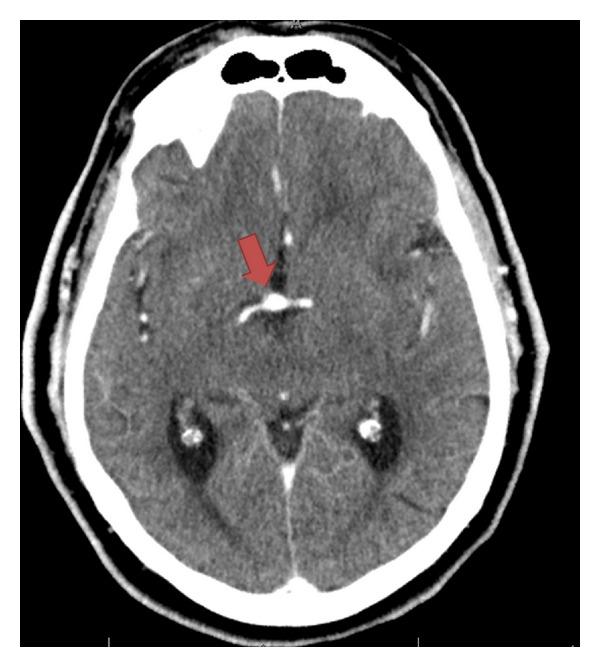

Large basilar aneurysm with posterior inferior cerebellar artery stroke and consequential fatal subarachnoid hemorrhage.

Basilar artery aneurysm presenting a stroke is rare, and we present a case of this along with a discussion of the management options available.

以卒中为表现的基底动脉动脉瘤很罕见,我们在此报告一例,并讨论现有的治疗选择。